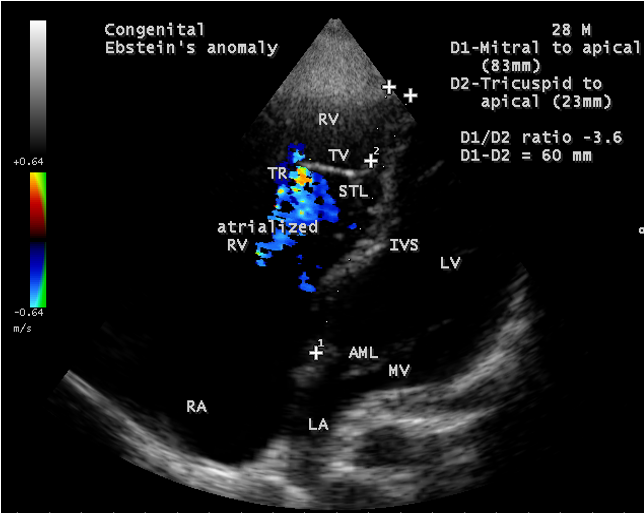

A 28-year old male presented with cyanosis and auscultation revealed a ‘sail sound’ ( loud tricuspid component of first heart sound due to increased tension developed by the large anterior leaflet as it reaches the limits of its systolic excursion- an important sign of anterior leaflet mobility), a ‘cadence’ quality of quadruple rhythm due to wide splitting of first and second sounds ( due to complete right bundle branch block), atrial and ventricular filling sounds (summation of these sounds due to prolonged PR interval). ECG revealed the features of Ebstein’s anomaly as shown in Figures 11 and 12. X-ray chest revealed the Ebstein’s configuration as shown in Figure 13. 2D echocardiography revealed a ‘sail-like’anterior tricuspid leaflet forming a ‘muscular curtain’ in between the inflow and trabecular parts of the right ventricle as an ‘imperforate membrane’ with a ‘pinhole’communication, associated with a muscular VSD (ventricular septal defect) in the proximal, atrialized compartment of right ventricle suggesting an ‘atretic” (‘imperforate’) Ebstein’s anomaly as shown in Figures 14 to 27.

Echocardiographic features Echocardiography is the diagnostic test of choice for Ebstein’s anomaly and the first echocardiographic diagnosis was reported by Lundstrom in 1969. The first diagnostic criteria for Ebstein’s anomaly using a multi-crystal two-dimensional system was defined by Hagan in 1974 [33] and they were able to recognize the apical displacement of the septal tricuspid leaflet and an elongated anterior tricuspid leaflet with increased excursion. The septal leaflet of the tricuspid valve attaches chiefly to the ventricular septum , but part of its basal attachment is to the posterior wall of the right ventricle [34] and it normally exhibits a slight but distinct apical displacement of its basal attachment to the central fibrous body compared to the mitral valve. The distal displacement of septal origin of tricuspid valve seems to be the best echocardiographic criterion as the characteristic sign for Ebstein’s anomaly and the degree of maximal displacement in normal hearts varies considerably with a mean difference of approximately 6 mm with mitral valve. To define the anatomic severity of Ebstein’s anomaly, four-chamber view is the best to demonstrate the apical displacement of septal tricuspid leaflet [35]. The ratio between the mitral-to-apex distance and the tricuspid-to-apex distance varies from 1 to 1.2 in normal subjects and 1.8 to 3.2 in patients and it is 3.6 as in Figure 18 with Ebstein’s anomaly. The true distance in the level of insertion of atrioventricular valves is obtained by substracting the tricuspid-to-apex distance from the mitral-to-apex distance with a mean value of 27.25 ± 12 mm in patients with proven Ebstein’s anomaly and it is 60 mm as shown in Figure 18 compared to reference group (5.7 ± 2 mm). Kambe and coworkers calculated the distance between both atrioventricular valves directly as a mean value of 21 mm with a range of 14 to 32 mm [36]. A maximum difference in the level of valve insertion of >15 mm in children and >20 mm in adults is discriminated between normal and Ebstein’s anomaly [37],[38]. Despite this fact, a patient with an ‘unequivocal’ Ebstein’s malformation can be encountered in whom the diagnosis cannot be made with certainity solely on the basis of apical displacement of the septal tricuspid valve leaflet. Occasionally, the leaflet attaches to the trabecular part rather than the inlet part of the septum, the conventional four-chamber view will not reveal any septal insertion as shown in Figures 28 and 29.

The anterior tricuspid leaflet is not involved in the process of downward displacement, it may be abnormally inserted occasionally and Shiina, et al documented the apical displacement of anterior tricuspid leaflet in 14% of cases echocardiographically [39]. The anterior leaflet forms a large, sail-like intracavitary curtain as in Figures 14, 25 and contains muscular strands instead of consisting entirely of a fibrous membrane as in the normal tricuspid valve [40]. It is potentially mobile with a brisk sail-like movement as shown in Figure 21 to 24 [41], free bloating with a ‘whipping motion’ across the right ventricular outflow tract (RVOT) as shown in Figure 26 and in some cases, the movement is restricted due to its adherence to the ventricular wall as in Figure 1 and 2, 4 and 9. It is often fenestrated, may in part be musculaized , inserting into the trabeculations of the right ventricle (RV) as in Figure 28 and rarely, the anterior leaflet forms an ‘atretic’ membrane that spans the midportion of the right ventricular cavity as in Figure 16.

The tricuspid orifice is typically incompetent as in Figures 3, 5 and 10, occasionally stenotic, and rarely imperforate as in Figure 16 [44],[45]. The true anatomic tricuspid annulus occupies its normal position at the right atrioventricular junction and it is less well defined than in a normal heart. The annulus tends to be appreciably dilated and contribute to the development of valvular incompetence. In extreme downward displacement of posterior and septal leaflets, the closure of the tricuspid annulus depends on the size and potential excursion of anterior leaflet. When the chordal attachments are short and the leaflets contain multiple or large fenestrations, adequate valve closure is impossible to achieve and varying degrees of regurgitation results. Color flow imaging and Doppler interrogation can establish the relatively low velocity regurgitant flow as in Figure 6, which begins at the level of the displaced septal and posterior leaflets as in Figures 5 and 10 and courses through the atrialized right ventricle into the right atrium proper as shown in Figure 5. Tricuspid regurgitation increases by annular dilatation [46]. During contraction of the atrium, the atrialized portion of the right ventricle balloons out and acts as a passive reservoir. Functional improvement of right ventricle depends on the severity of tricuspid regurgitation and on the ratio of the combined areas of right atrium and atrialized right ventricle relative to the areas of functional right ventricle and left ventricle [47]. Celermajer, et al described an echocardiographic grading score for neonates with Ebstein’s anomaly as shown in the Table 5 [48].

Ebstein’s original case was an example of obstruction at the tricuspid orifice by a membrane dividing the right ventricle into two halves as shown in Figure 16 of a 28-year old cyanotic male with ECG and X-ray characteristics as in Figure 11 to 13. suggesting an advanced spectrum of Ebstein’s malformation , necessitating RV exclusion techniques such as Starnes’ procedure. The florid case of Ebstein’s anomaly with the insertion of leaflet tissue along with ventricular walls as a ‘blanket’ as in Figures 28 and 29 in a 30-year old cyanotic male may go for an initial palliation with bidirectional Glenn shunt (cavopulmonary anastomosis). The other variants of moderate degree of leaflet tethering with varying degrees of regurgitation, but an intact basal leaflet attachments with atrioventricular junction as in Cases 1 and 2 may need a definite repair. In Ebstein’s mitral valve as in Figure 32 in a 10-year old boy, the downward displacement of functional annulus > 0.8 cm/m2 is not particularly striking and tends to affect the septal leaflet (anterior mitral leaflet) alone. The valve is thickened and mildly regurgitant due to rheumatic involvement rather than an anatomic cause.